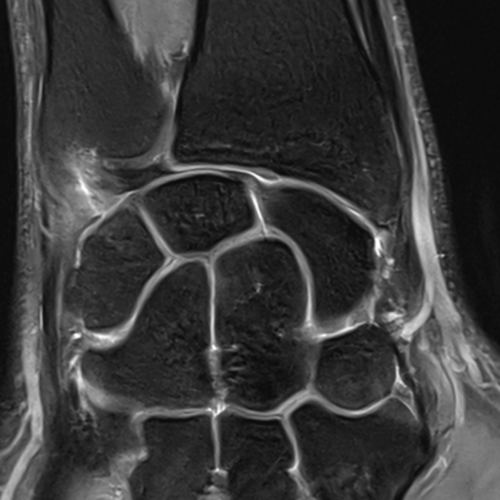

Quand pratique-t-on une IRM du poignet ?

Cet examen est réalisé en cas de douleurs, traumatismes pour analyser :

• les os du poignet :

Scaphoïde

Lunatum (semi-lunaire)

Triquetrum (pyramidal)

Pisiforme

Trapèze

Trapézoïde

Capitatum (grand os)

Hamatum (os crochu)

Quels sont les résultats possibles d’une IRM du poignet ?

Cette examen permets de diagnostiquer:

• Fractures du poignet notamment fracture du scaphoïde

• Entorses et lésions ligamentaires : ligament scapho lunaire, luno triquétral, bascule en DISI, ligament triangulaire du carpe TFCC

• Pathologies nerveuses : syndrome du canal carpien

• Pathologies tendineuses : notamment tendinite de De Quervain

• Pathologies articulaires : arthrose, polyarthrite rhumatoïde

• Nécrose osseuse : maladie de Kienböck

• Kystes du poignet